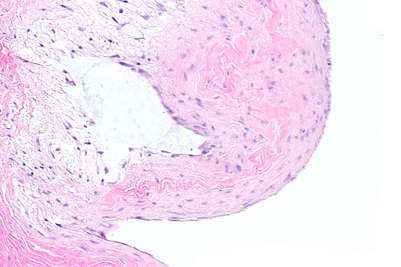

Ganglion cyst - space with myxoid material. Secondary inflammatory changes